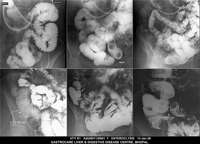

Section: ENTEROCLYSIS Total: 205 images

BaM Enteroclysis Loopogram BaE Fistulogram Urethrogram HSG